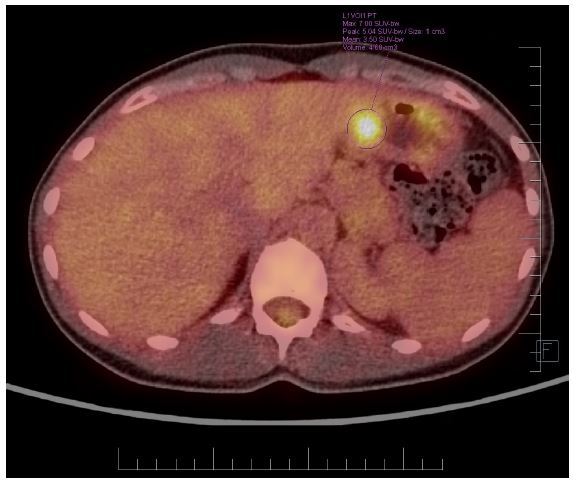

Nevertheless, the patient was assessed by a colorectal Multidisciplinary Team (MDT) at Masaryk Memorial Cancer Institute (MMCI), which decided on adjuvant therapy for the stenotic tumour. Adjuvant chemotherapy on the base of 5 fluorouracil (FU/FA Mayo) was administered. However, this was converted to monotherapy capecitabine due to an allergic skin reaction and neutropenia grade IV. Further therapy was uncomplicated, and close follow-up was recommended. An elevation of tumour marker Carcinoembryonic Antigen (CEA) of 21,8 μg/l was found in October 2017. However, a normal level of the Carbohydrate Antigen (CA) 19-9 of 25.2 ng/ml was noted. Subsequent assessment revealed a left ovarian mass with suspicion of a metastatic process. In November 2017, the patient underwent a gynaecologic evaluation followed by explorative laparotomy at the Department of Gynaecology in the University Hospital Brno. A hysterectomy with bilateral oophorectomy and appendectomy was performed, and malignant ascites was also found. Histological findings showed metastases of moderately differentiated intestinal adenocarcinoma in the left ovary (Figure 1b), identical to the primary transverse colon tumour resected in 2013. KRAS, NRAS and BRAF gene mutations were not detected. The postoperative recovery was uncomplicated, and the patient was referred back to medical oncologists at MMCI. A follow-up Positron Emission Tomography/Computed Tomography (PET/CT) scan was performed in December 2017. It discovered a small metabolically active lesion measuring 12 mm located in the pyloric region closer to the gastric, small curvature (Figure 2). Tumour marker CEA was again slightly elevated (9,4 μg/l) (Figure 3). A gastroduodenoscopy showed prominent gastric walls in the region of the angular notch without mucosal changes. A biopsy was taken, and histologic examination revealed benign atrophic gastritis only (Figure 4).

Figure 2: Positron Emission Tomography/Computed Tomography (PET/CT) scan discovered a small metabolically active lesion measuring 12 mm – PET ‘‘active” focus - located in the antrum and pyloric region closer.